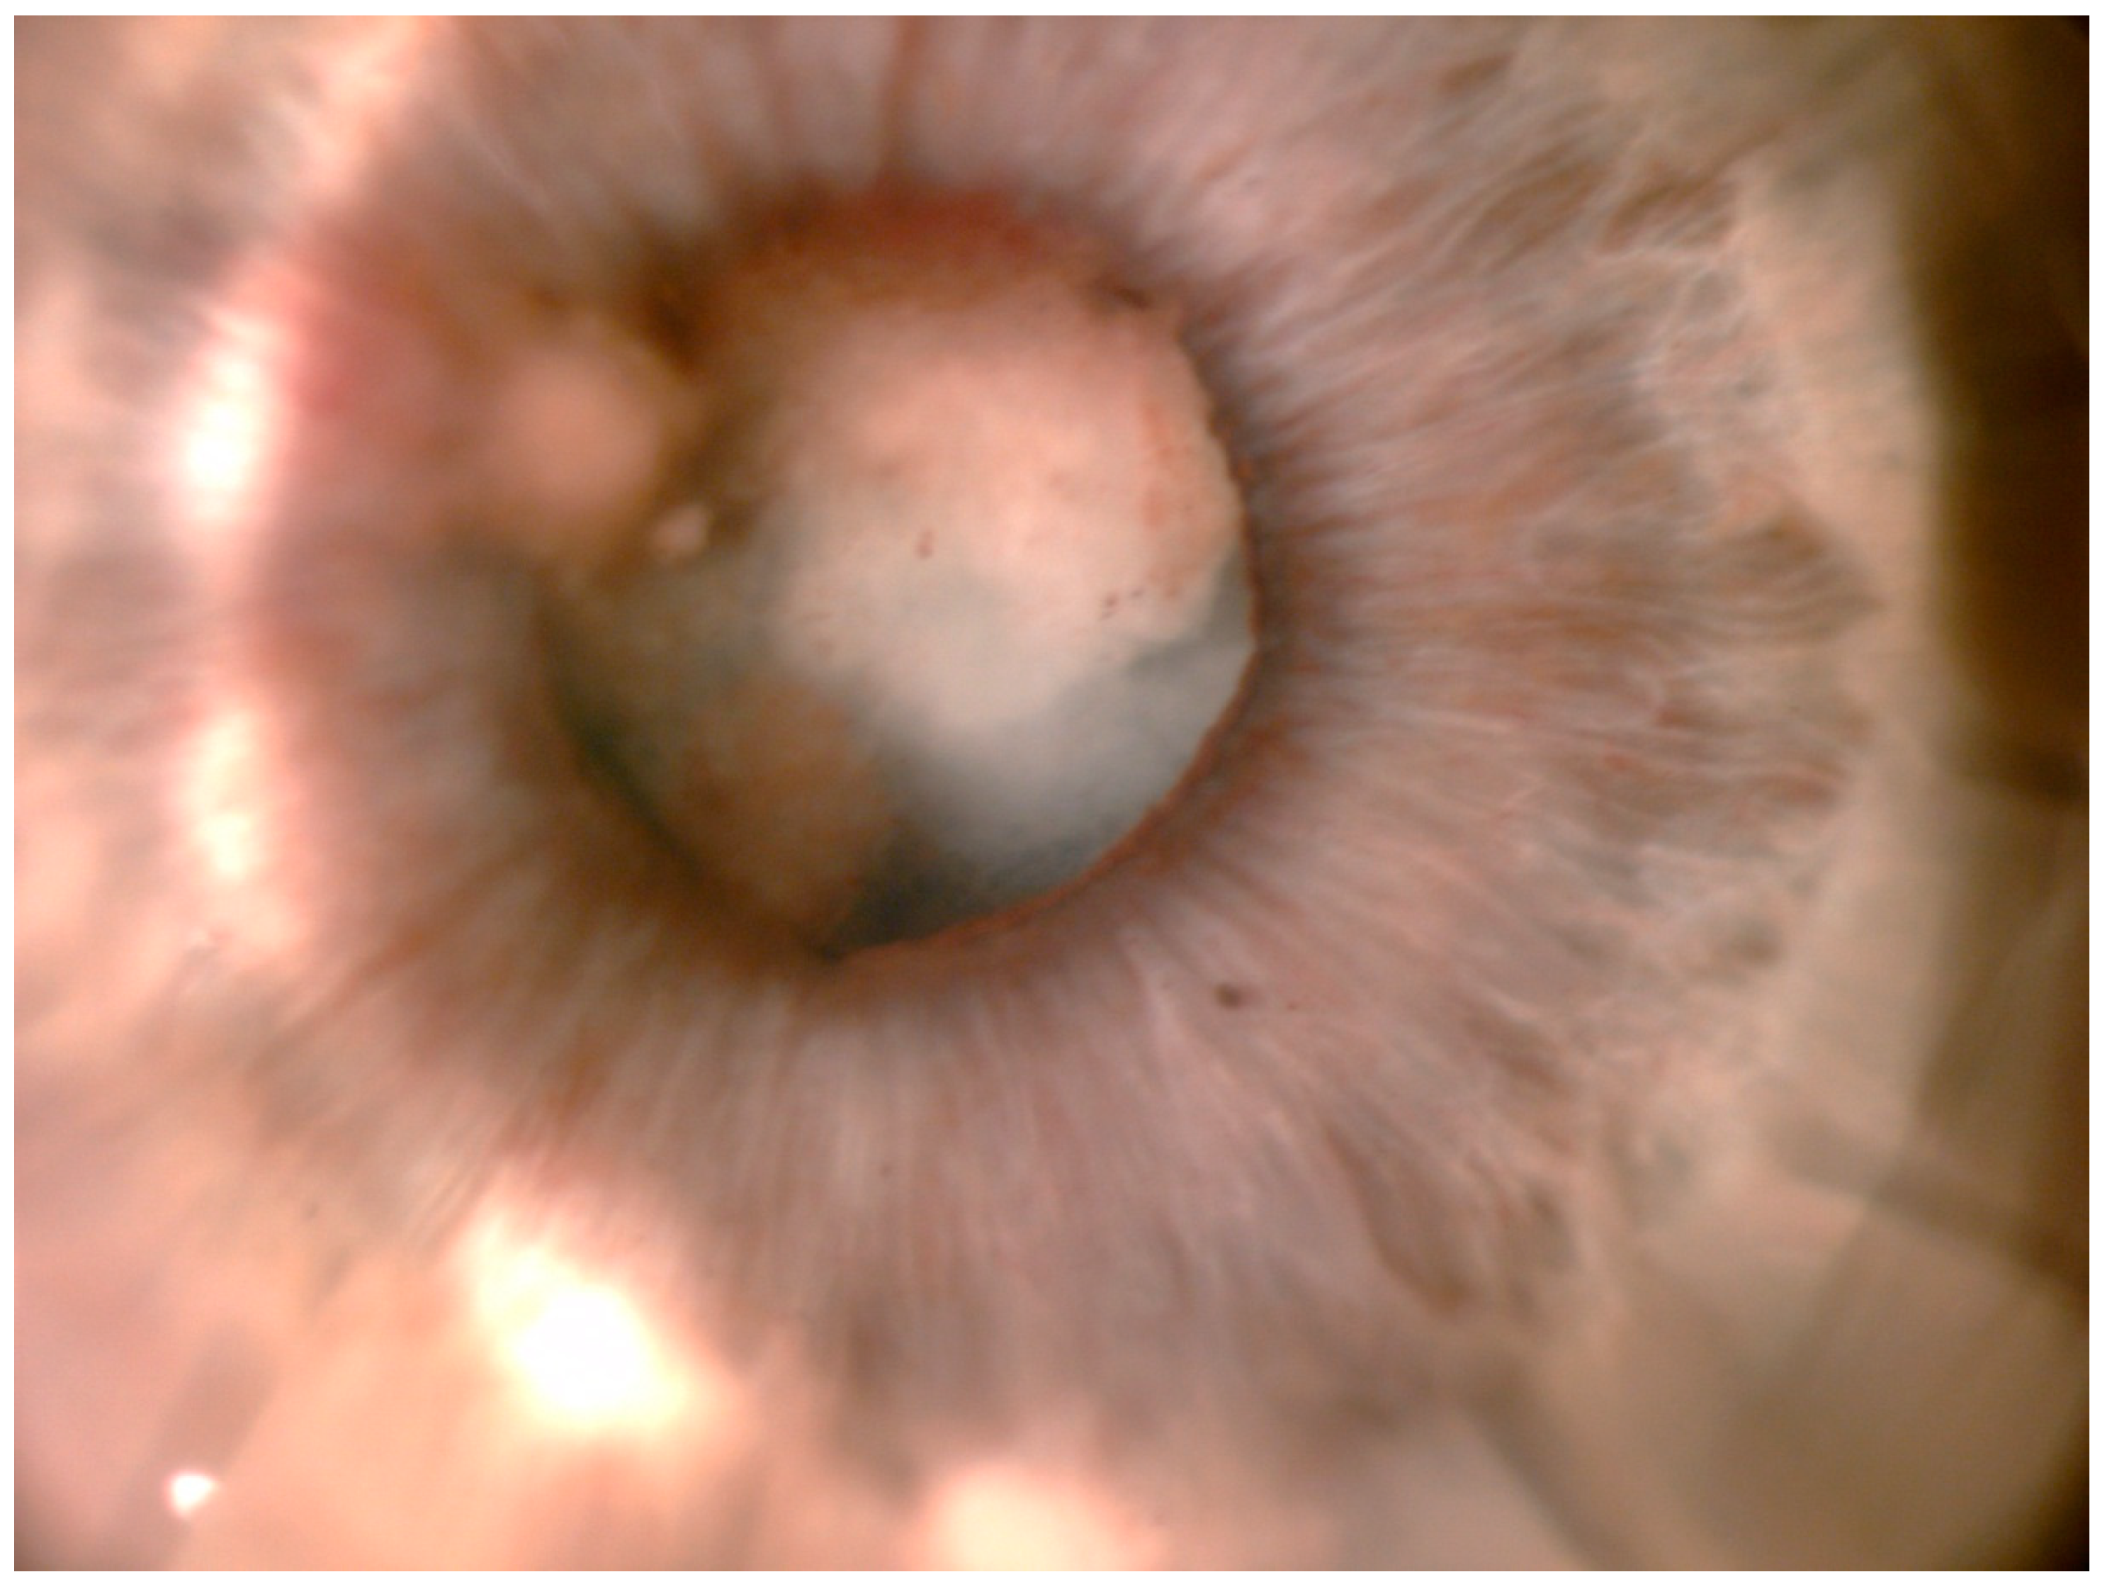

3. Results